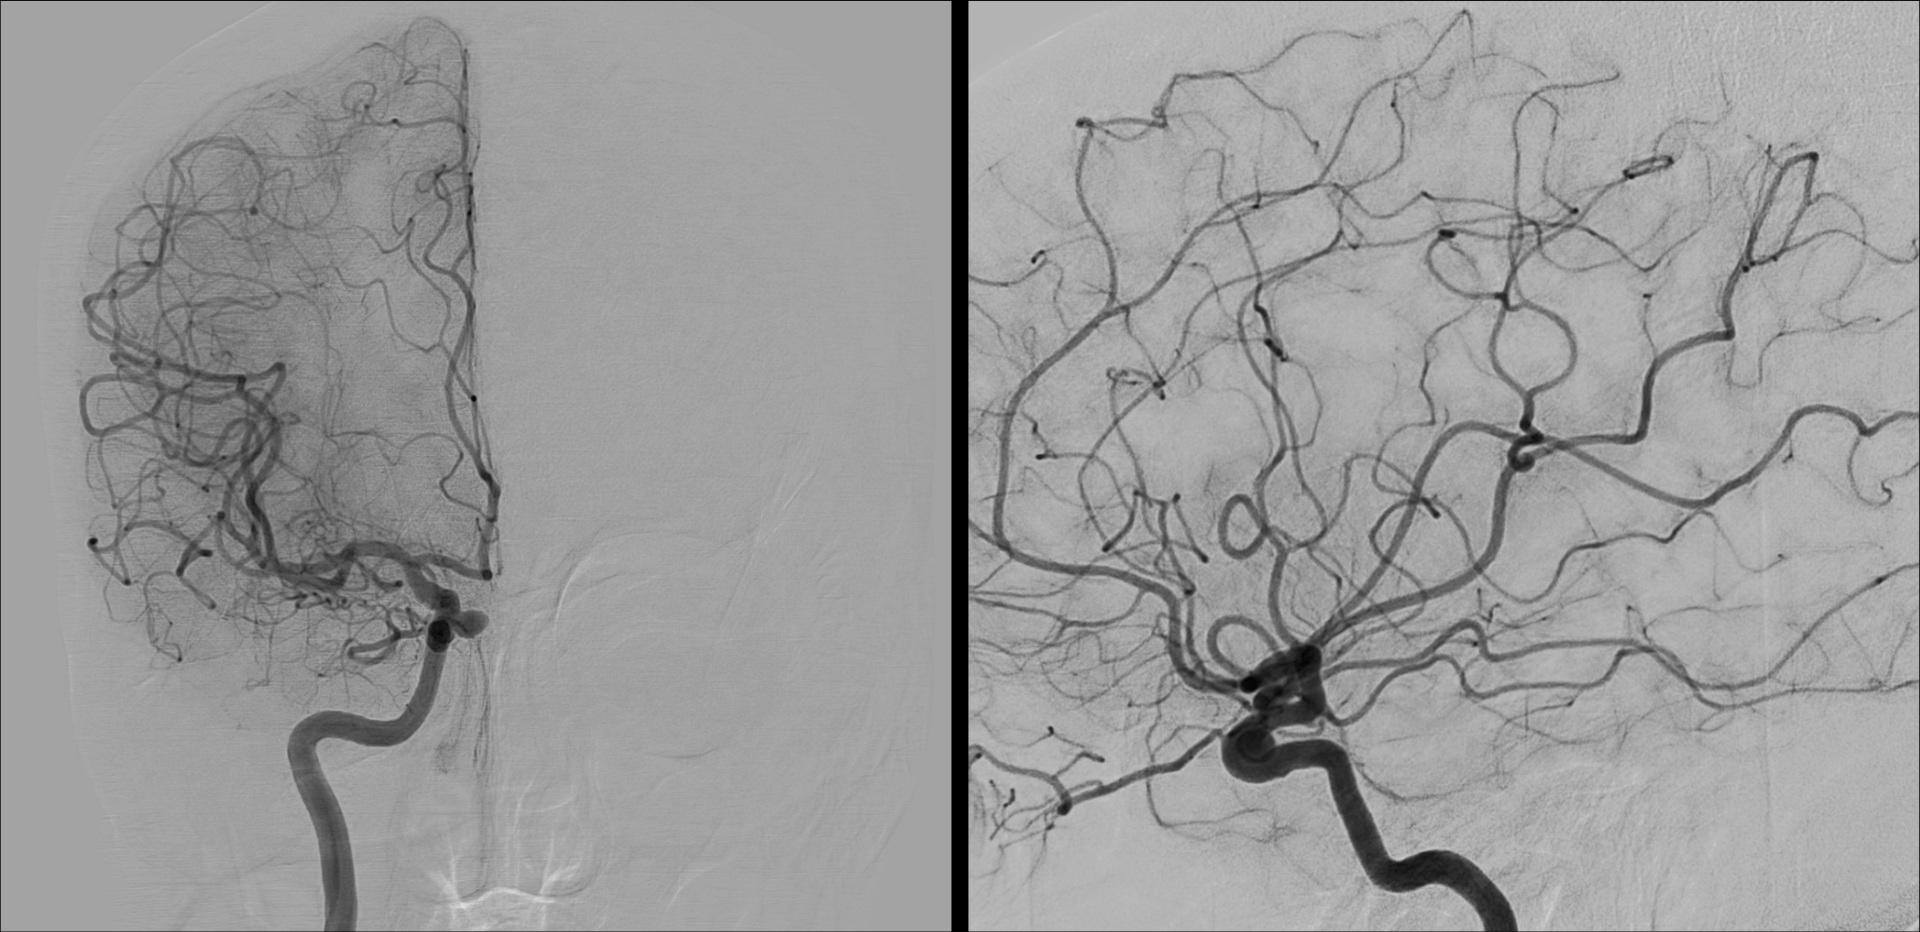

En angiographie cérébrale diagnostique, les protocoles d’injection de produits de contraste iodés pour l’évaluation des anévrismes non rompus gagneraient à être standardisés. Telle est la conclusion d’une étude réalisée par une équipe d’imagerie médicale du CHU de Strasbourg, menée par le manipulateur radio Nicolas Dehlinger. L’étude en question, publiée dans Radiography il y a quelques jours [1], avait pour objectif de passer en revue les pratiques actuelles et de révéler la variabilité des paramètres d'injection, en soulignant l'absence de protocoles standardisés et les conséquences potentielles sur la sécurité des patients et la qualité des images.

Cette idée de recherche lui est venue de sa pratique, où Nicolas Dehlinger a constaté que les protocoles d’injection en angiographie diagnostique pour les anévrismes cérébraux non rompus répondaient souvent à une logique empirique. « C’est de l’héritage entre pairs et il n’y avait pas vraiment de ju